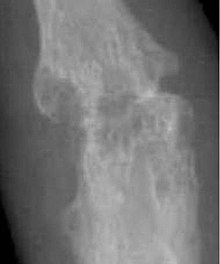

| A hand affected by rheumatoid arthritis, an autoimmune form of arthritis | |

Rheumatoid arthritis (RA) is a disorder in which the body's own immune system starts to attack body tissues.[32] The attack is not only directed at the joint but to many other parts of the body. In rheumatoid arthritis, most damage occurs to the joint lining and cartilage which eventually results in erosion of two opposing bones. RA often affects joints in the fingers, wrists, knees and elbows, is symmetrical (appears on both sides of the body), and can lead to severe deformity in a few years if not treated. RA occurs mostly in people aged 20 and above. In children, the disorder can present with a skin rash, fever, pain, disability, and limitations in daily activities.[33] With earlier diagnosis and aggressive treatment, many individuals can lead a better quality of life than if going undiagnosed for long after RA's onset.[34] The risk factors with the strongest association for developing rheumatoid arthritis are female sex, family history of rheumatoid arthritis, and exposure to tobacco smoke.[35]

Bone erosion is a central feature of rheumatoid arthritis. Bone continuously undergoes remodeling by actions of bone resorbing osteoclasts and bone forming osteoblasts. One of the main triggers of bone erosion in the joints in rheumatoid arthritis is inflammation of the synovium, caused in part by the production of pro-inflammatory cytokines and receptor activator of nuclear factor kappa B ligand (RANKL), a cell surface protein present in Th17 cells and osteoblasts.[36] Osteoclast activity can be directly induced by osteoblasts through the RANK/RANKL mechanism.[37]